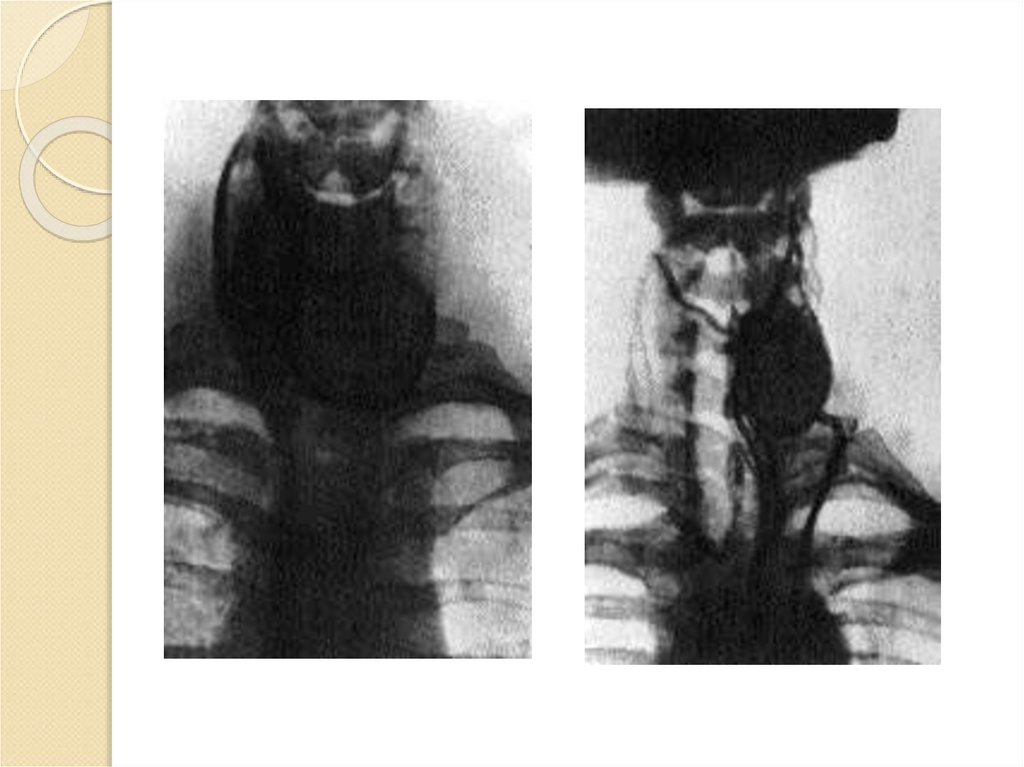

Рентгенограмма загрудинного пространства с

конрастированным пищеводом при

подозрении на загрудинное расположение ЩЖ

26. Сканирование щитовидной железы

Позволяет определить функциональную активность её ткани

по количеству захватывания радиоактивных веществ –

изотопов. Чем больше попало изотопов, тем больше сигнал,

тем выше активность. Для проведения сканирования

щитовидной железы обычно используют два изотопа:

радиоизотоп йода-123 и пертехнетат технеция-99т. Как

правило, их вводят внутривенно, но в некоторых случаях через рот. Технеций используют чаще. Это вещество дешевле

и скорость распада быстрее, чем у йода-123.